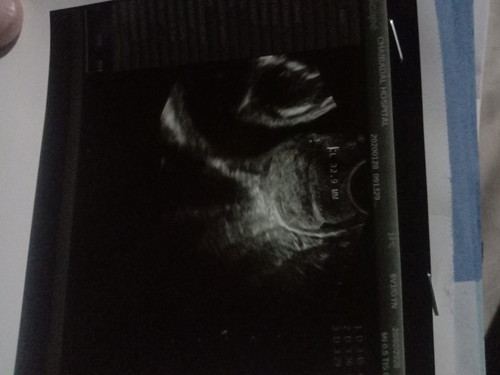

คือเราไม่รู้ว่ารู้นี้คืออะไรอะค้ะคุณเเม่คนไหนพอจะรู้มั้งรึป้าวค้ะ

เป็นใบซาวแบบ 2 มิติค่ะตัวนี้เราจะมองไม่เห็นน้องนอกจากคุณแม่จะไปซาวด์แบบ 3 หรือ 4 มิตินะคะตอนนี้คุณแม่จะเห็นได้เฉพาะน้ำหนักของน้องค่ะ.